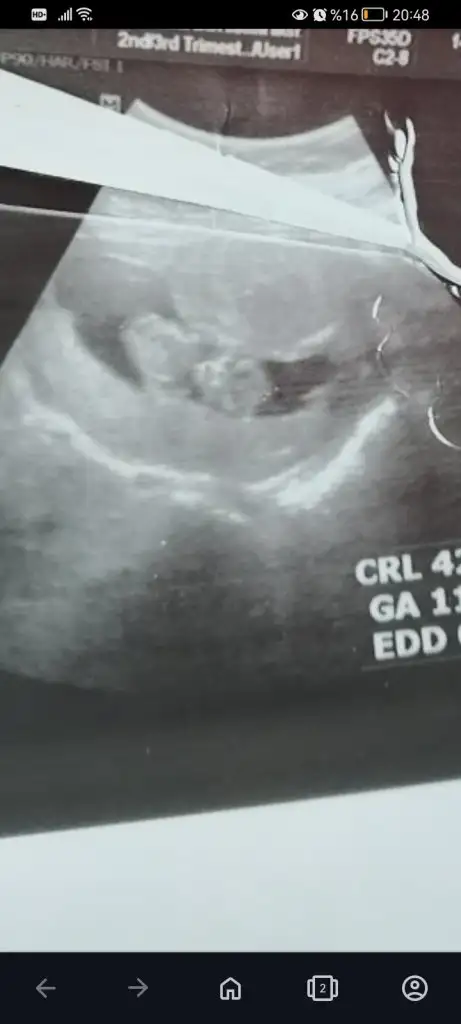

13+6 nubu kız gibi ama bacak arasında da çıkıntı var gibi sizin tahmininiz nedir

Eklentiler

• Screenshot_2023-11-21-20-22-33-531_com.miui.gallery.webp

17,7 KB · Görüntüleme: 126

• Screenshot_2023-11-21-20-21-29-746_com.miui.gallery.webp

19 KB · Görüntüleme: 116

• Screenshot_2023-11-21-20-20-53-023_com.miui.gallery.webp

18,8 KB · Görüntüleme: 105